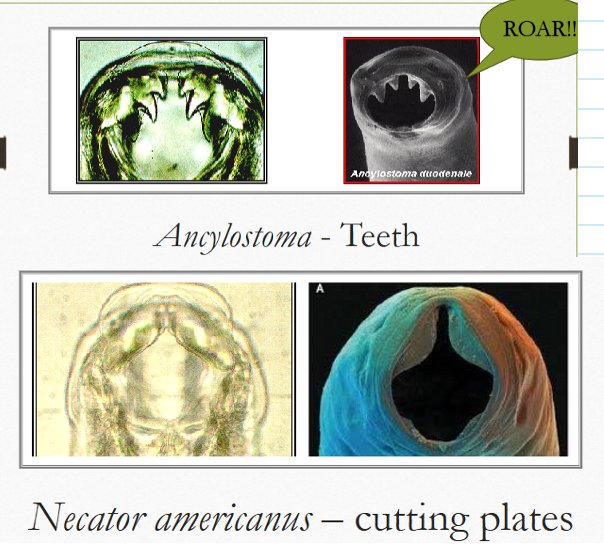

difference between ancylostoma teeth & necator teeth?

ancylostoma = pointy teeth

necator = cutting plates / looks like manatee